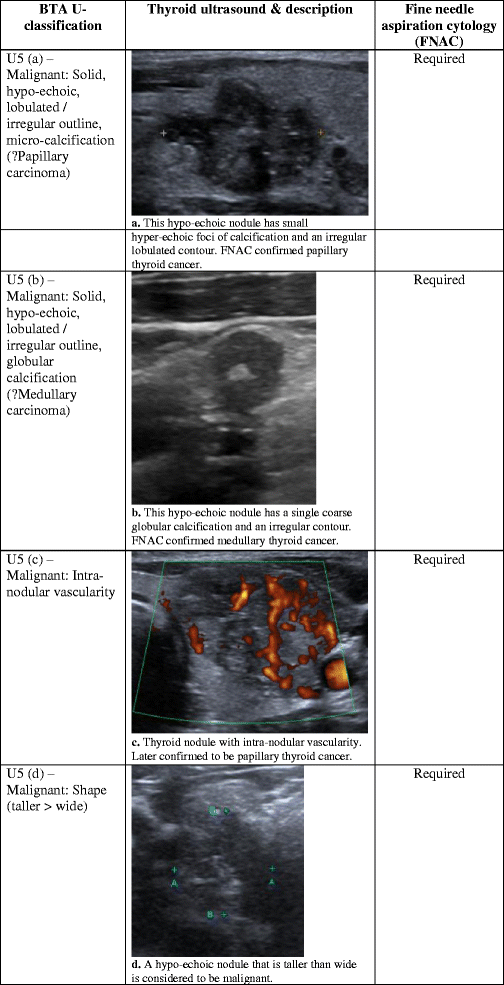

Ultrasonography Of Thyroid Nodules A Pictorial Review

Racgp Differentiating Between Benign And Malignant Thyroid